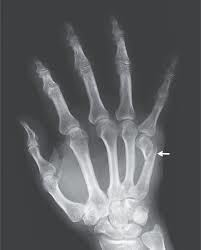

what is this?

subungual haematoma